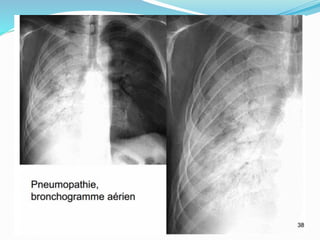

Pneumopathies infectieuses

Opacité alvéolaire avec

bronchogramme aérien

Pneumopathies infectieuses Fig 1: Opacité alvéolaire systématisée Opacité alvéolaire avec bronchogramme aérien